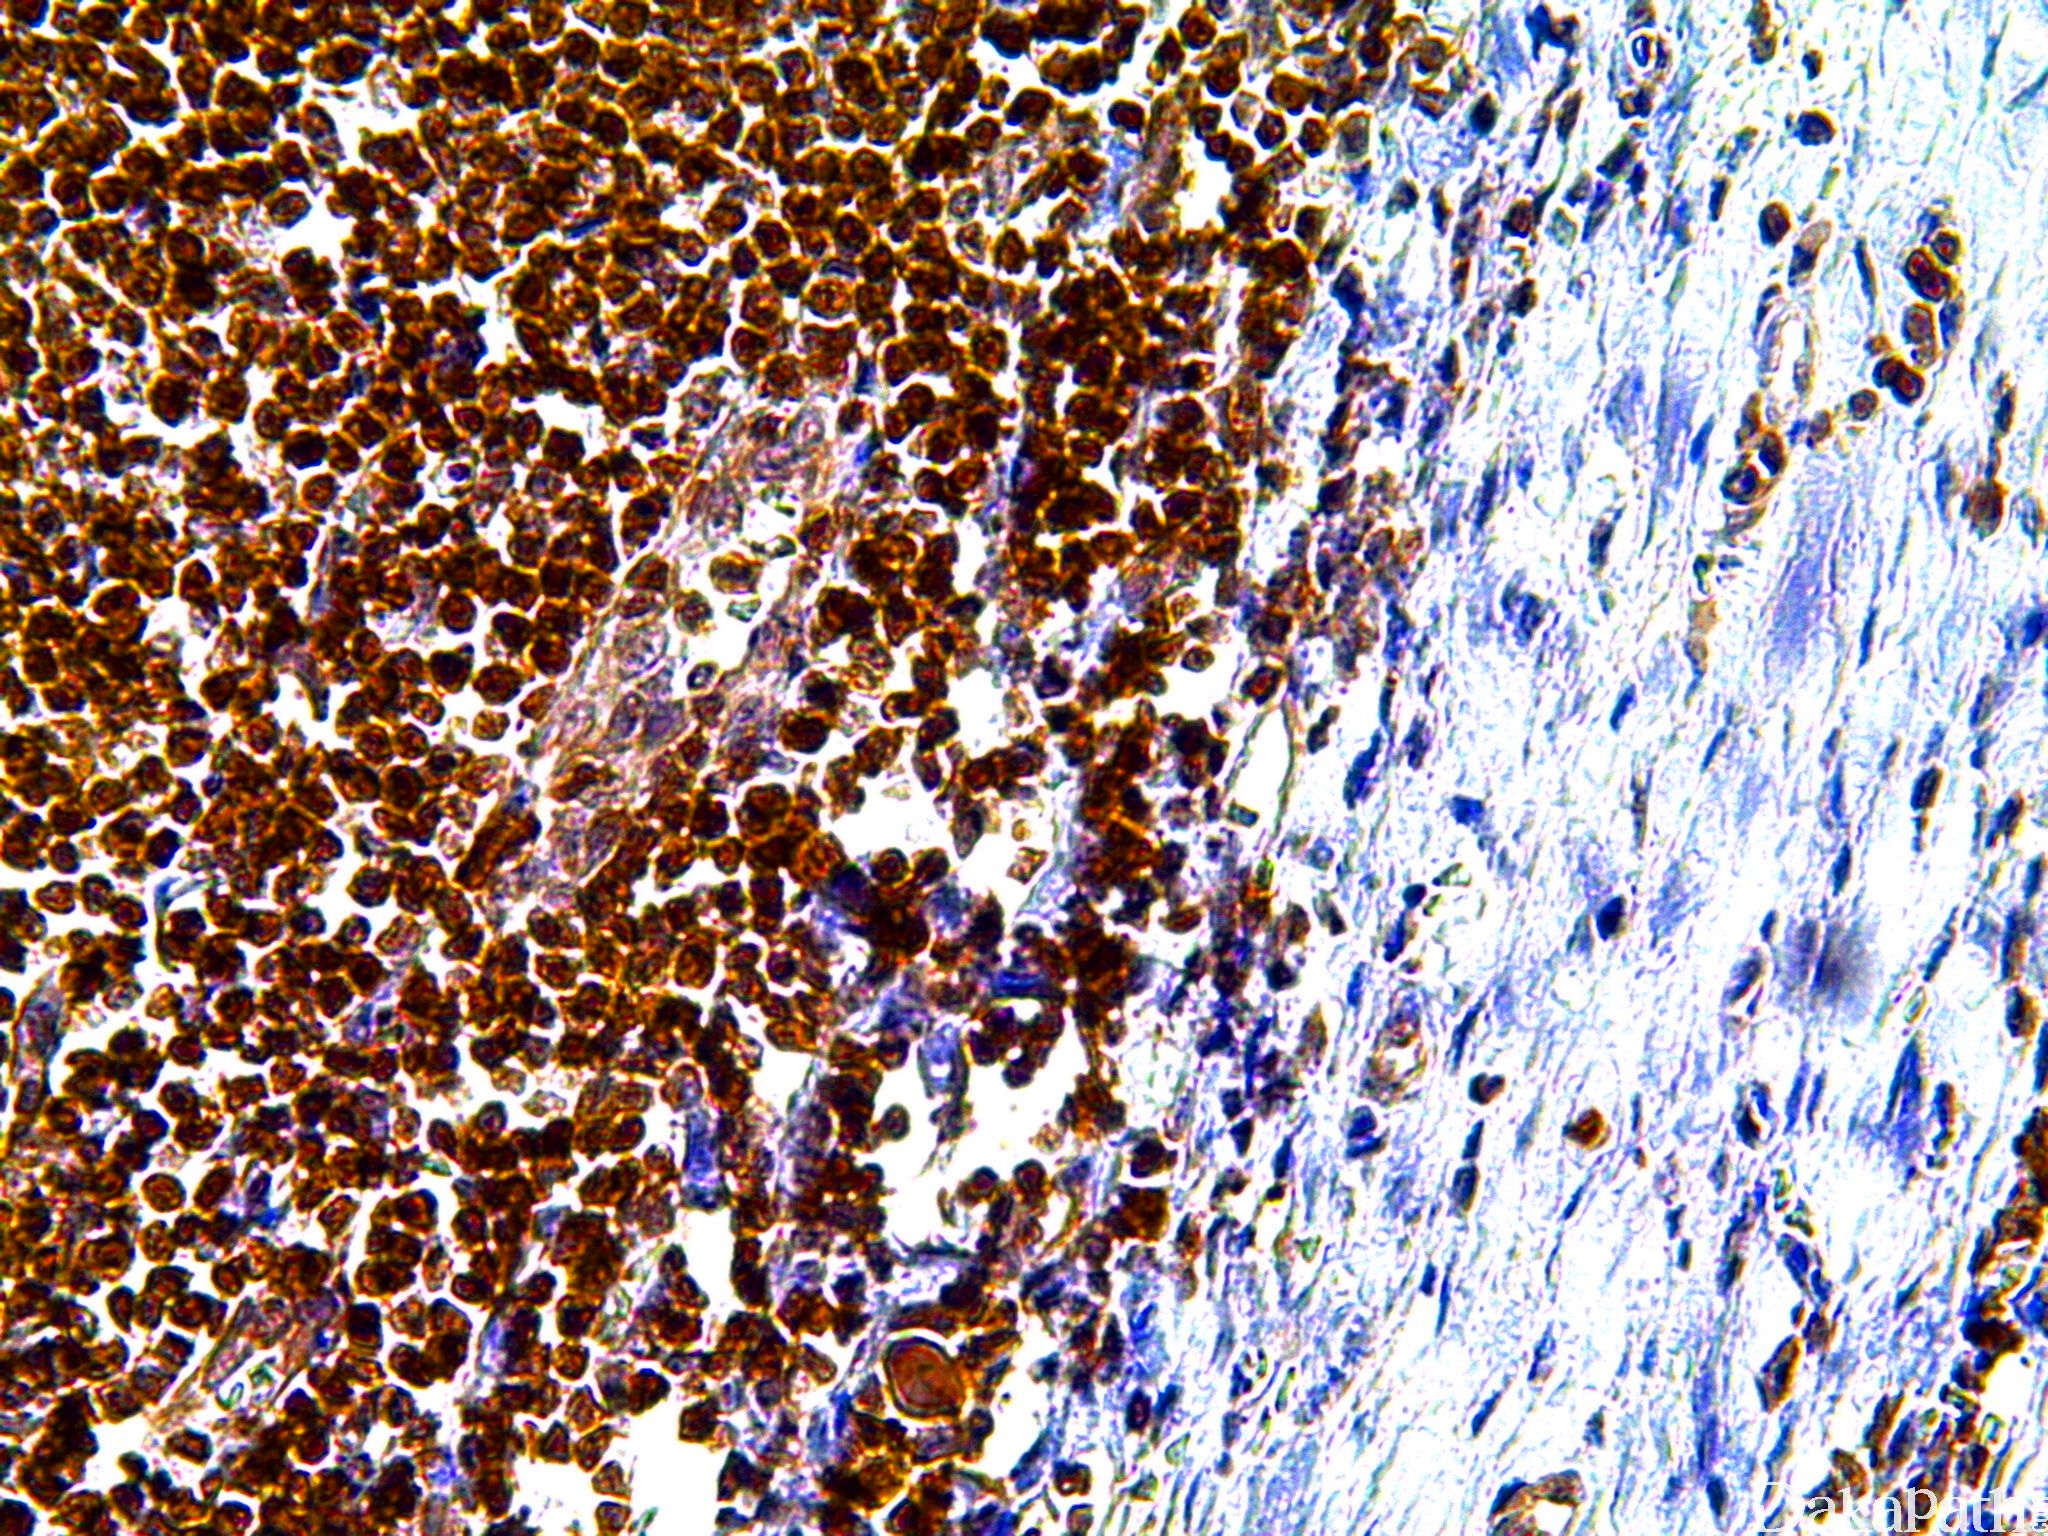

P27

细胞周期依赖激酶抑制剂,其表达与乳腺癌等肿瘤预后有关。

信号定位: 胞核

在肿瘤中的表达情况:

几乎全部阳性(≥95%的病例阳性): 膀胱尿路上皮癌、滤泡性淋巴瘤、滤泡性淋巴瘤 I 级、胰腺实性假乳头状肿瘤、乳腺导管原位癌、异型增生性痣、原发性渗出性淋巴瘤,HHV-8 相关、脾脏边缘区淋巴瘤、恶性肌上皮瘤、边缘区 B 细胞淋巴瘤、甲状腺非典型腺瘤、多形性腺瘤、慢性淋巴细胞白血病/B 小淋巴细胞淋巴瘤